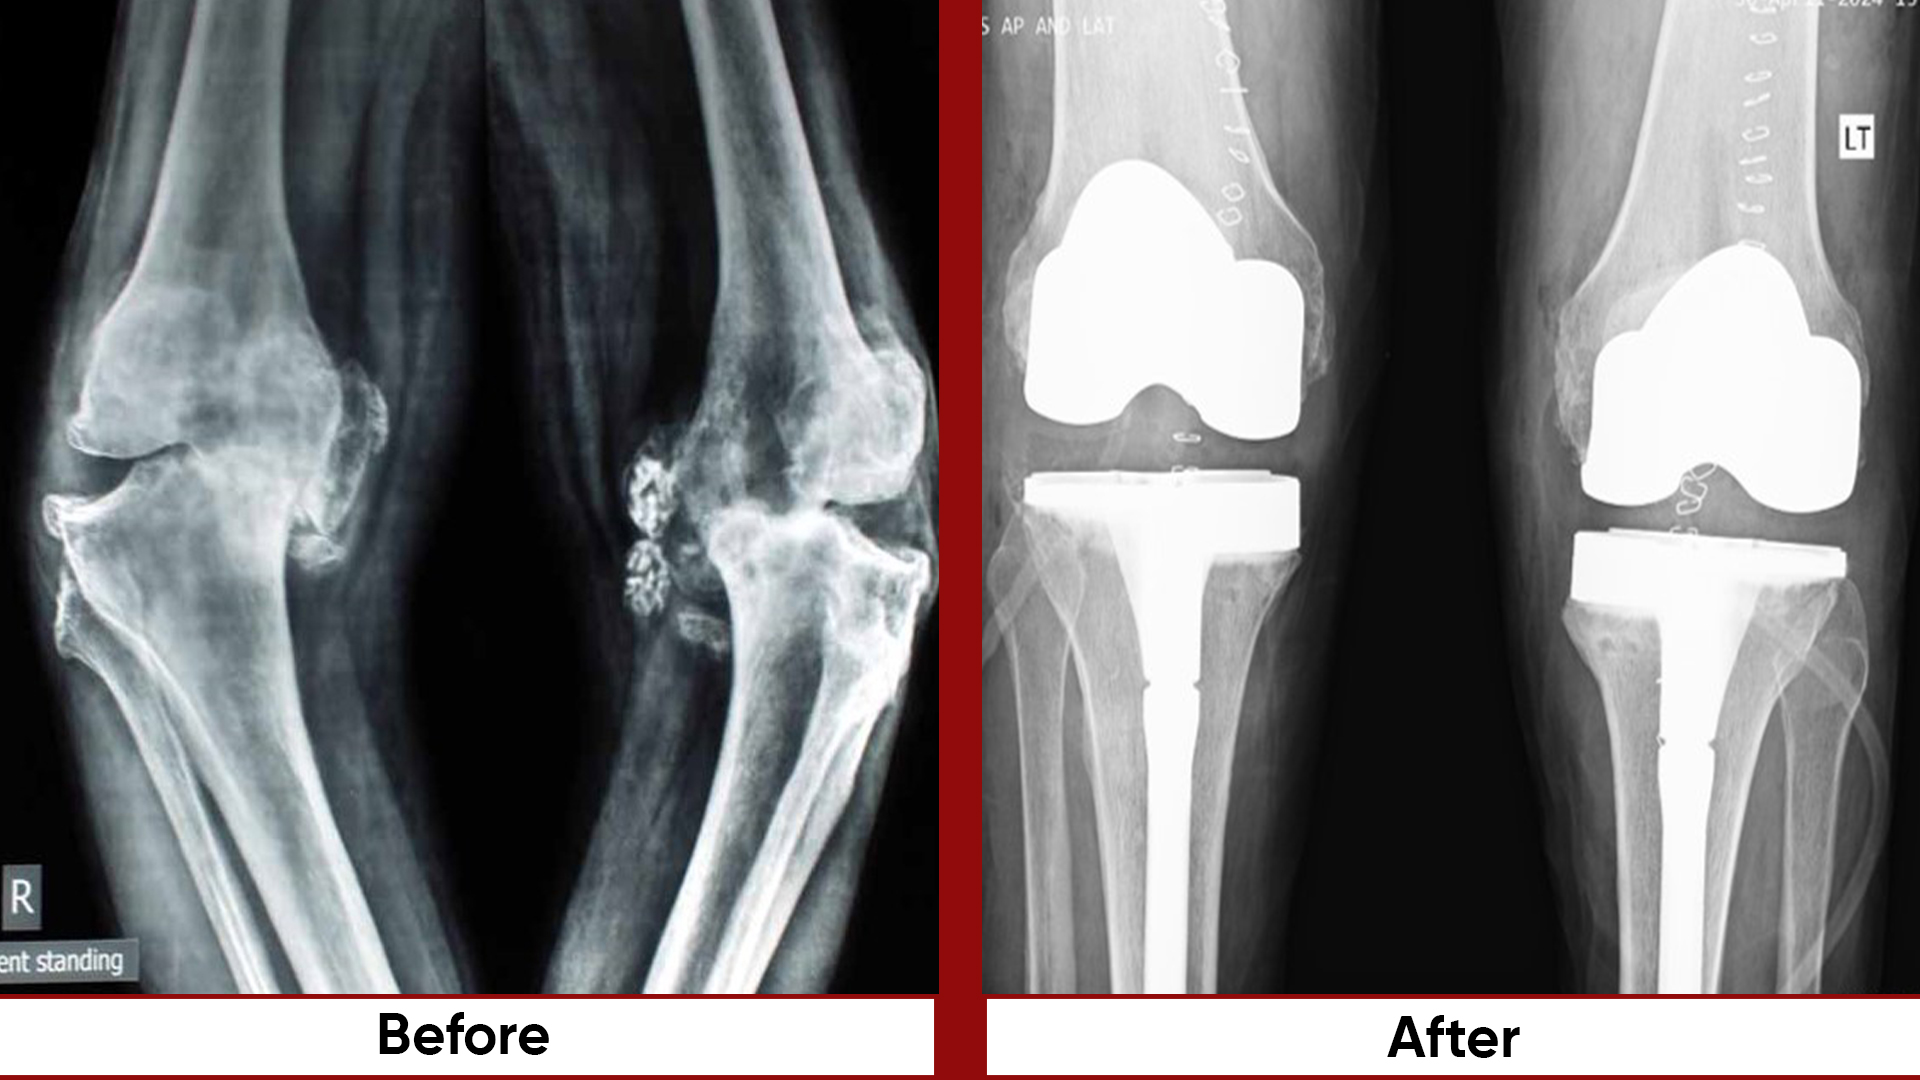

• Total Knee Replacement (TKR)

• Deformity Correction (limb lengthening, bowlegs, knock knees)

• Osteotomies (bone realignment surgeries)